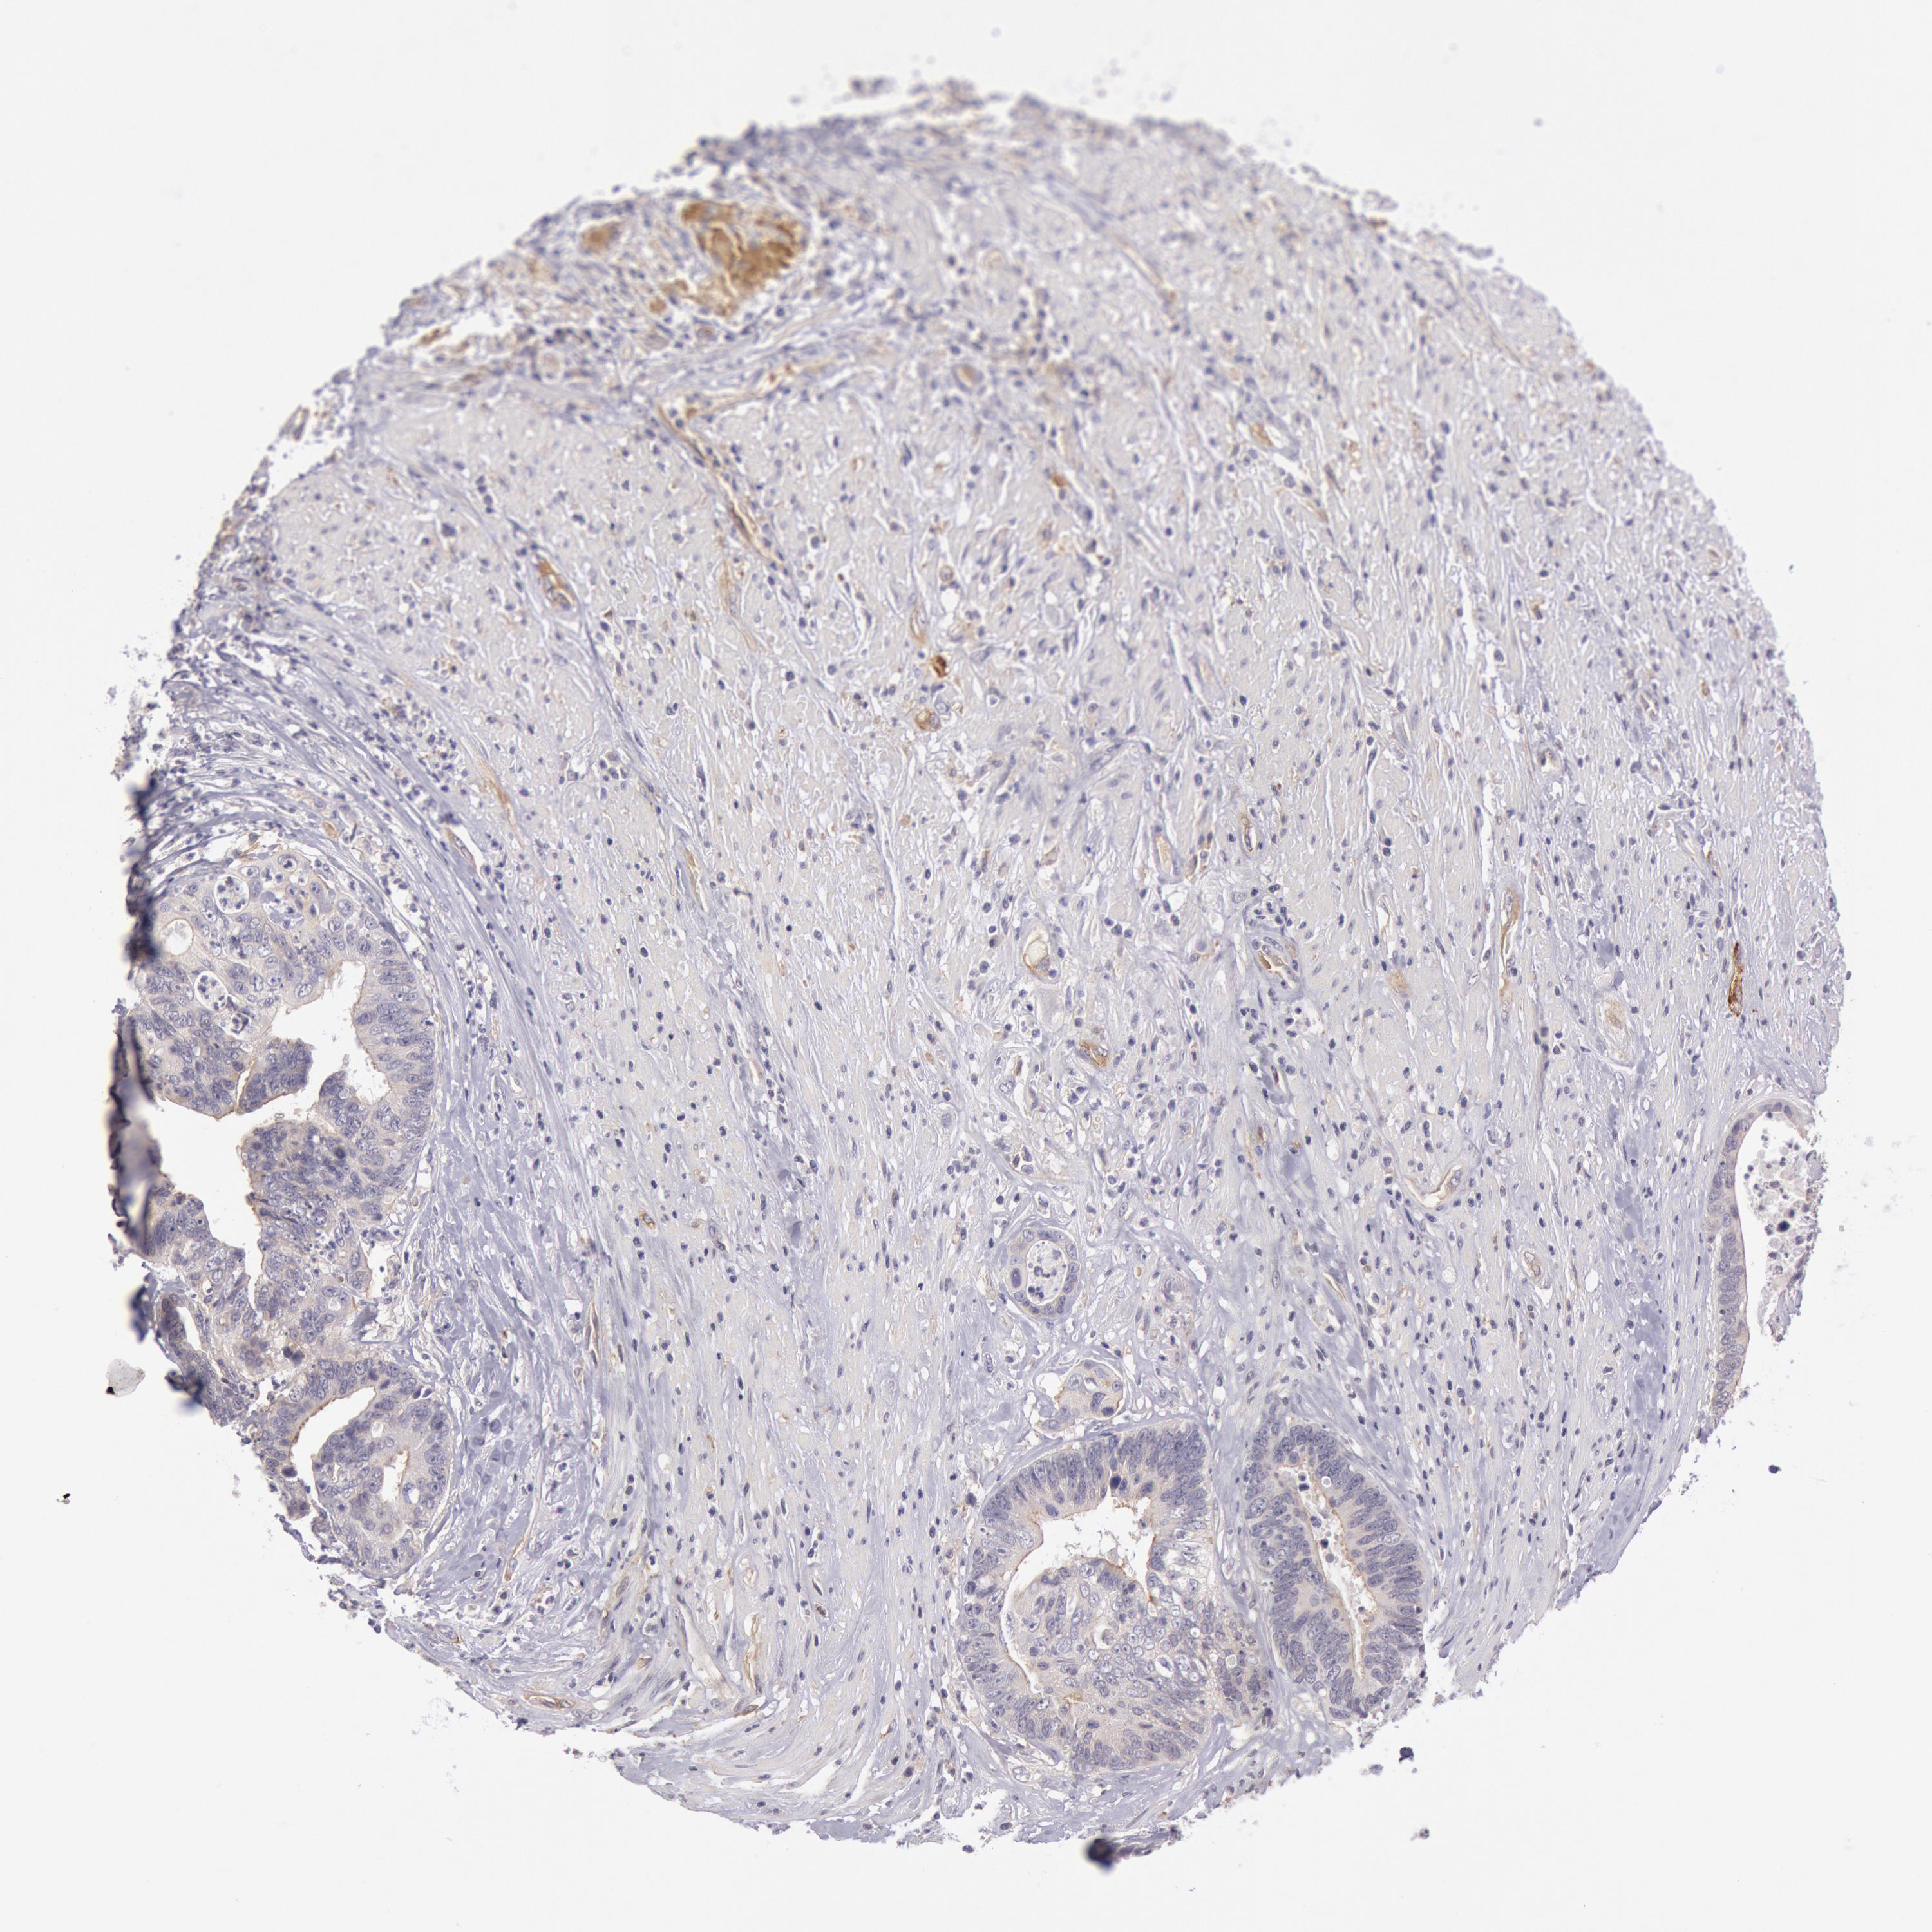

CANCER COLORECTAL CANCER Show tissue menu

Colorectal cancer

Human cancer

Colon adenocarcinoma

Rectum adenocarcinoma